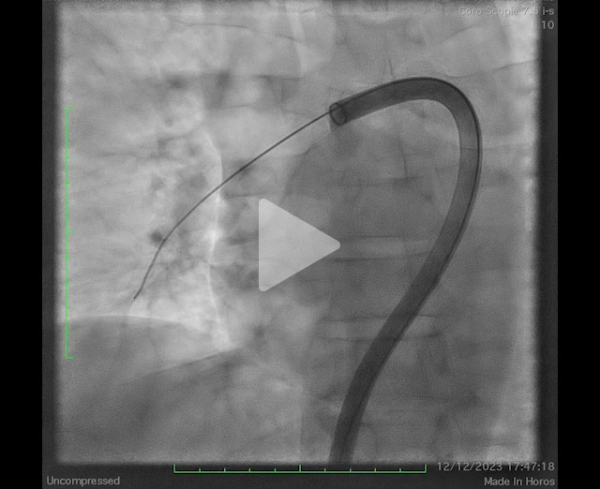

Il s’agit d’une procédure réalisable sous anesthésie locale, par voie fémorale écho-guidée (introducteur de grand diamètre – 24F) et sous monitoring de l’efficacité de l’héparinothérapie. Une cathétérisation sélective des 2 branches de l’artère pulmonaire est réalisée permettant la confirmation d’une hypertension pulmonaire initiale (mesurée à ici à 67mmHg pour la PAPs) (Figure 8), la mise en place d’un cathéter dédié de thromboaspiration permettant de ramener le thrombus (Vidéos 2, 3 et 4). À visée d’épargne sanguine, chaque aspiration est filtrée pour permettre une réinjection du sang.

Vidéo 2 : angiographie initiale

Vidéo 3 : persistance thrombus occlusif troncus antérieur après aspiration

Vidéo 4 : contrôle après aspiration